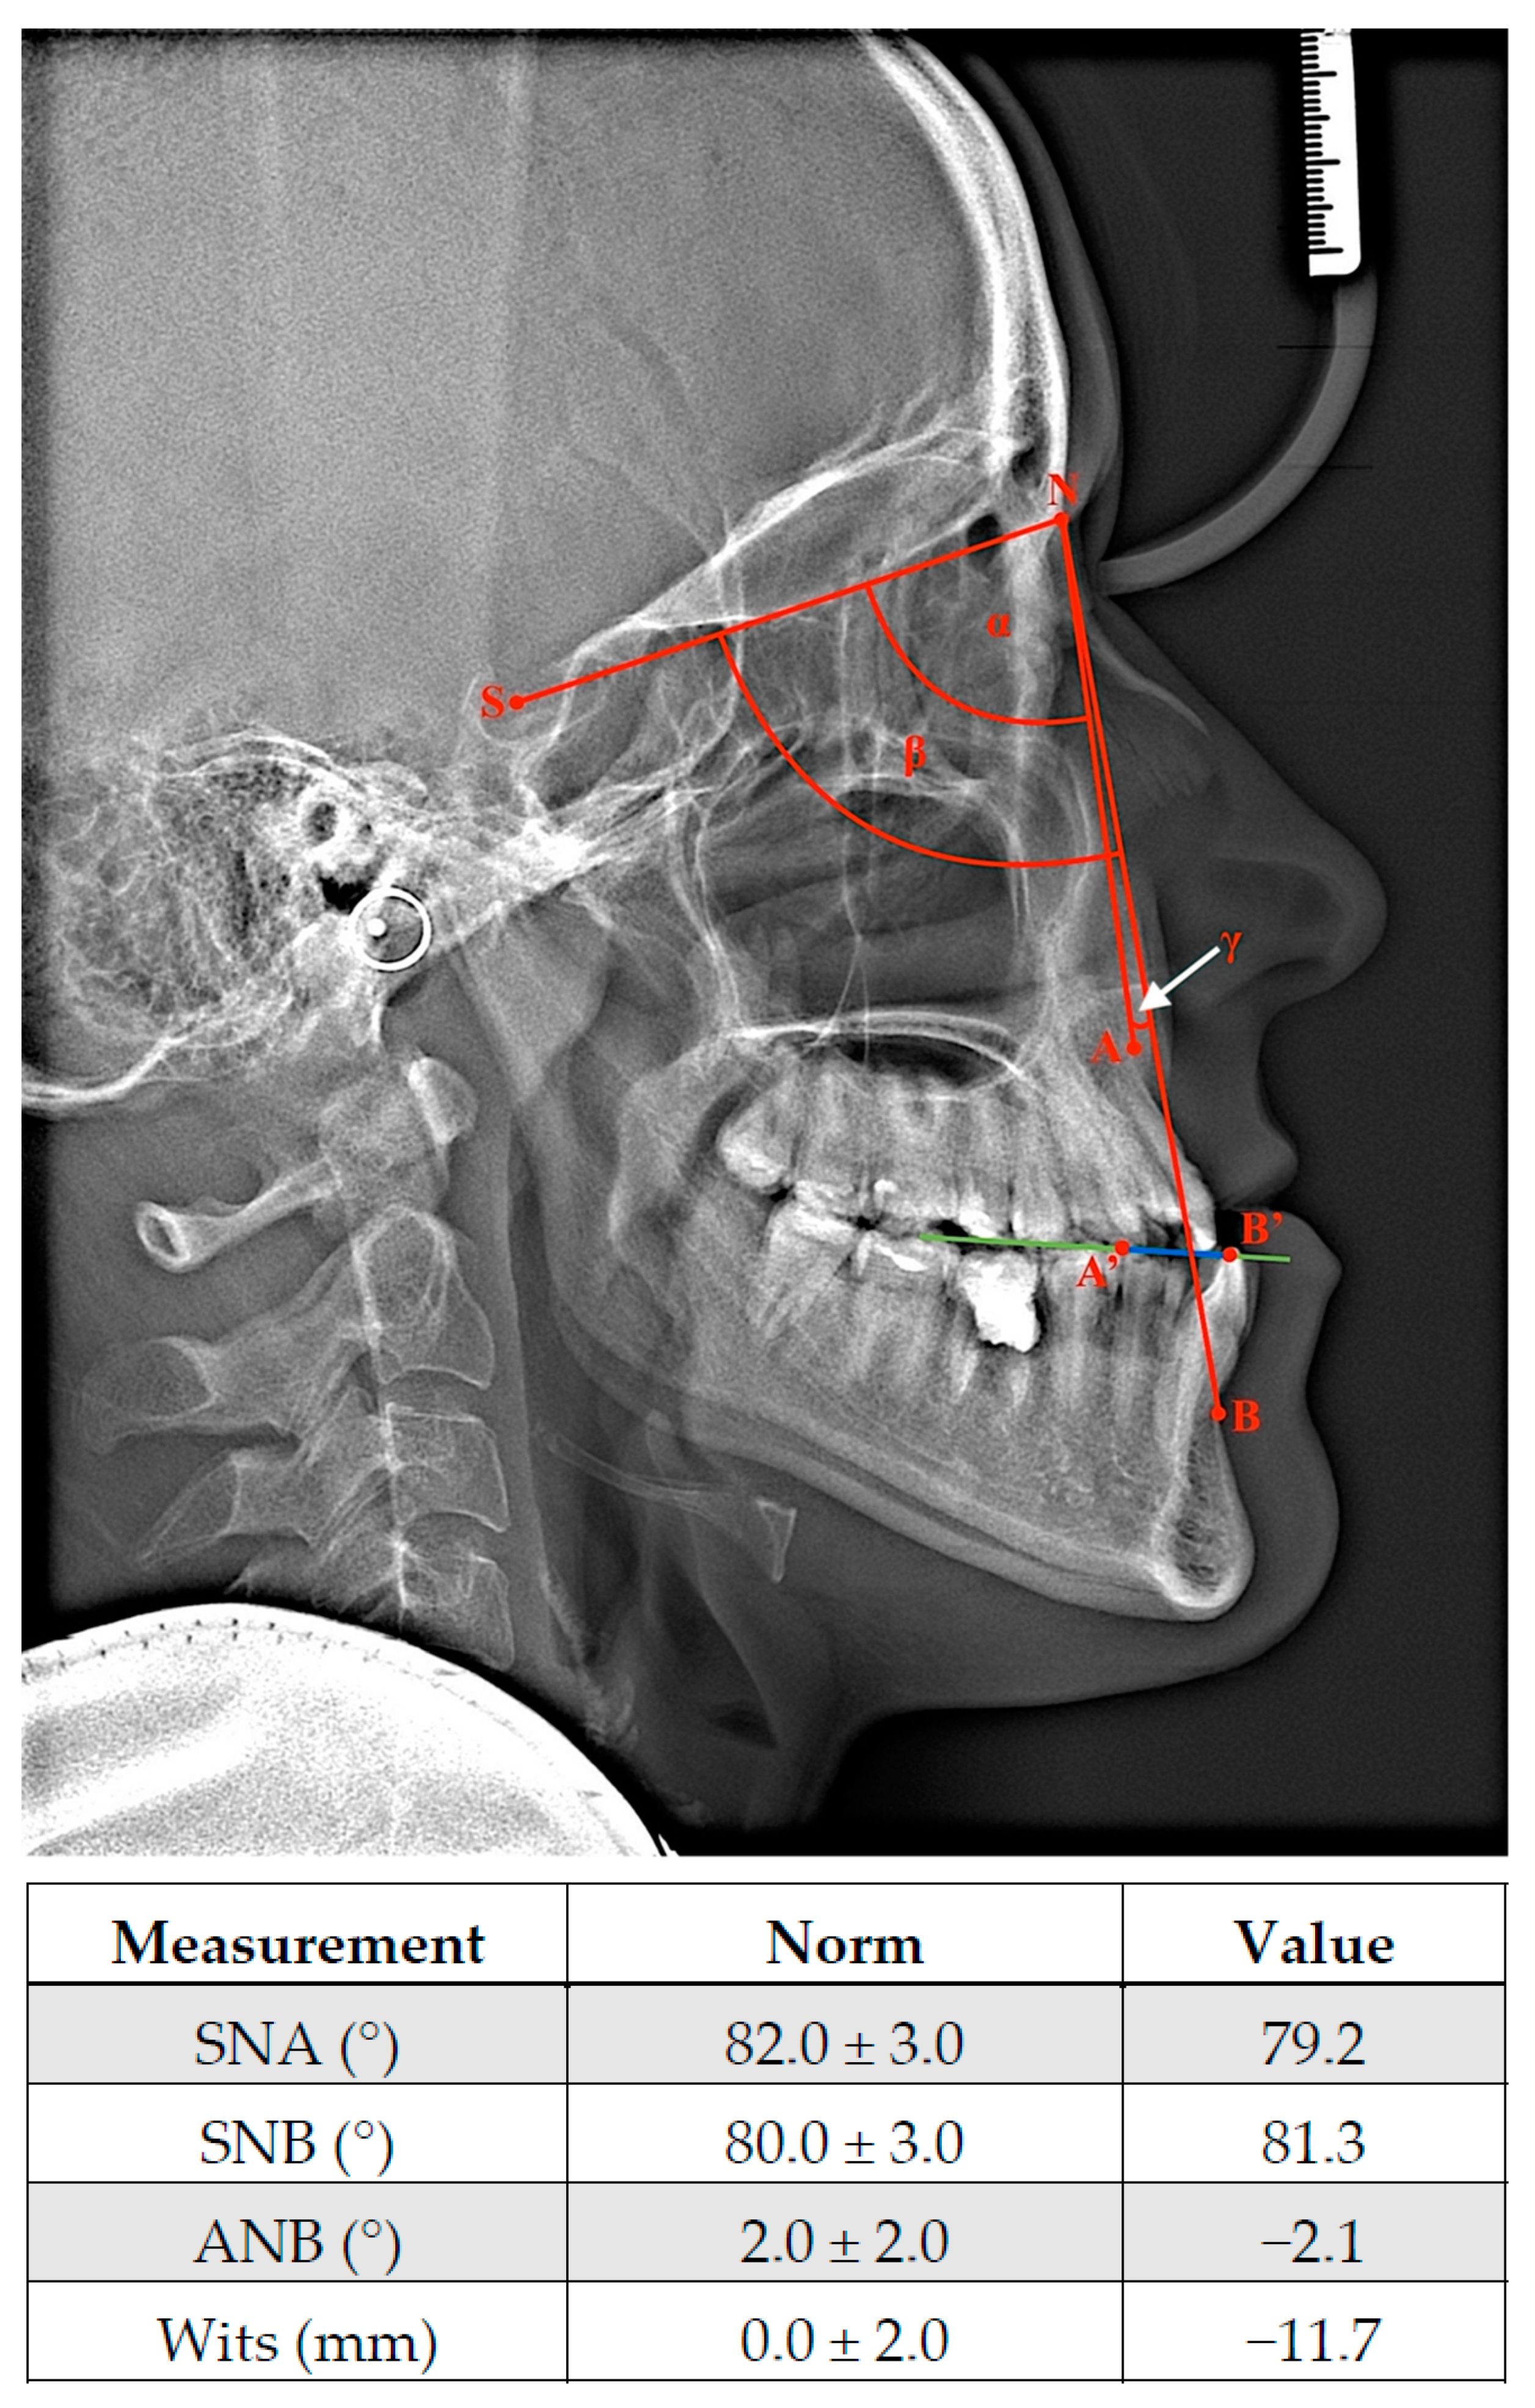

Morphometric analyses of facial profile provide information about potential gnathic defect in patients. Specifically, the concave profile, protrusion, and extension of the lower facial area are measured [79]. In extreme cases, long face syndrome can appear as part of the class III malocclusion phenotype [80], where the relationship between the upper and lower lip is distinctly disturbed. Due to an average 2 mm retrusion and potential atrophy of the upper lip, the eversion of the lower lip, difficulties with proper lip contact, or even a lack of connection between them may be observed [81]; these additionally reduce chin prominence and decreasing of depth of labiomental fold [80]. MP is manifested on the midface, and the paranasal area, nasolabial fold, and cheek line are flattened [7]. Due to the complex nature of the stomatognathic system, each growth irregularity forces changes within teeth position and thus occlusal status. During intraoral inspection, angle class III and canine class III with negative incisional overjet and reduced overbite are observed [74]. Moreover, open bite (anterior or complex) and cross bite (unilateral or bilateral) may be accompanied in the clinical image of MP. Interestingly, the occurrence of any dentofacial abnormalities leads to the activation of a compensatory mechanism aimed to restore functional balance within the orofacial region. Therefore, lower incisors are predominantly retroclined against proclined maxilla incisors. Additionally, modifications of the symphysis region and increased incisor eruption level may disproportionately compensate within the vertical dimension [82]. The potential coexistence of maxilla hypoplasia with MP may aggravate the abovementioned symptoms and clinical manifestations of class III skeletal malocclusion due to the posterior position of the upper jaw (Figure 1). Isolated maxilla deficiency can phenotypically provide similar features despite correct physiological mandibular proportions. It is worth noting that the skeletal conditioning of class III malocclusion may be ethnically different. It has been reported that in US population class III malocclusion mostly occurs as a maxillary hypoplasia and protrusion. In contrast, in Asians, this deformation is predominantly diagnosed with a normal upper jaw and the overgrowth of the mandible [83,84]. To avoid the misdiagnosis of improper upper jaw or mandible development, a lateral cephalometric radiograph with cephalometric analysis should be performed [84]; this is a standardized orthodontic method and a part of the diagnostic process of malocclusion and treatment planning. Angular and linear measurements carried out on a radiograph allow for the assessment of the positions of various anatomical structures [85]. Despite only analyzing skeletal relationship in the sagittal plane, this strategy determines which anomalies, dental or skeletal, underlie the disorder [86]. Angular and linear measurements carried out on a radiograph allow one to assess the anterior or posterior position of both jaws in relation to the anterior cranial base (Figure 2) [87]. A position on a cephalometric X-ray is marked by a line running from point S (midpoint of sella turcica; sella) to N (anterior end of nasofrontal suture, nasion). In turn, the localizations of the maxilla and mandible is indicated by point A (the most posterior point on the premaxilla in the midline and below anterior nasal spine; Subspinale) and point B (the deepest point in a fossa above chin; Supramentale), respectively [88]. Therefore, the value of angle between the SN and NA planes provides information regarding the sagittal position of the upper jaw in reference to the cranial base (82 ± 3°). In addition, the size of the angle created by the SN and NB allows one to lines assess the antero–posterior position of the mandible in comparison to the anterior part of the skull base (80 ± 3°) [89]. Both angles are recommended for measurements of retrognathism and MP in clinical practice [87]. Moreover, the evaluation of the mutual locations of mandible and maxilla plays a pivotal role in diagnosis and treatment planning as well. This relationship shows an ANB angle with a value for class I malocclusion from 0° to 4°. Thus, class II and III may be diagnosed when the value of ANB is above 4° and less than 0°, respectively. It is noteworthy that Wits appraisal, as a distance between point A and B projected onto an occlusal plane, may be also valuable for proper malocclusion diagnosis [90]. Physiological class I is in the range from −2 to 2 mm. Class II and III have Wits values of over 2 mm and less then −2 mm, respectively [91]. All of the abovementioned values have been presented according to Segner–Hasund’s cephalometric analysis [92].

Figure 1.

Representative 3D reconstructions of cone beam computed tomography (CBCT) examinations. Patient was diagnosed with class III skeletal malocclusion. (A) CBCT performed during pre-surgical orthodontic treatment. (B) Postsurgical treatment CBCT. The Le Fort I osteotomy of maxilla and the bilateral sagittal split osteotomy of mandible have been performed. The protrusion of maxilla and the retrusion of mandible were conducted to restore proper occlusal status. Osteosynthesis elements are visible (white) within both jaws.

Figure 2.

Representative cephalometric X-ray and part of cephalometric analysis according to Segner and Hasund presenting patients diagnosed with skeletal class III malocclusion before treatment. A-SNA; β-SNB; γ-ANB (white arrow); A’-B’0Wits (blue line); green line-occlusal plane. See the details description in text and Supplementary Materials section (Table S1) for all cephalometric measurements.